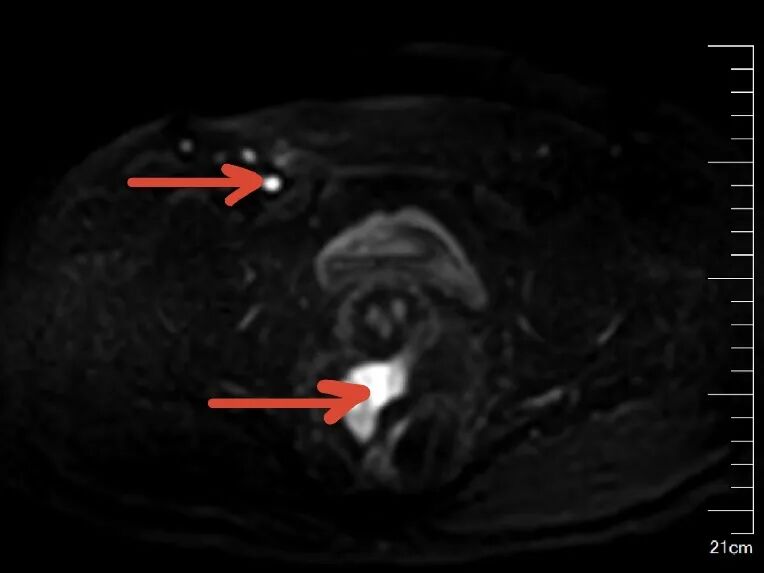

65岁的陈女士,因反复口干、多尿多饮、伴疲劳乏力,偶有胸闷,监测空腹指尖血糖超过11mmol/L,来我院内分泌科住院治疗,入院后完善相关检查,其中在子宫双附件彩超筛查中发现子宫上方见一类圆形低回声团,大小约37x32x37mm,边界不清,内部回声不均匀,这意味着不排除肿瘤可能。在积极控制血糖的同时,进一步完善了盆腔MR增强等针对性检查,结果提示:双侧附件区、

子宫直肠陷凹

及子宫周围多发结节状、团块状异常信号影,考虑附件区恶性肿瘤, 伴子宫直肠陷凹及子宫多发转移。内分泌科主任颜文盛考虑到该患者病情复杂,立即申请妇科会诊。经过妇科团队会诊,近期可能需要专科手术干预治疗,他与家属充分沟通后,家属果断选择转入广州市花都区人民医院妇科。

盆腔MR(红色箭头为转移病灶)